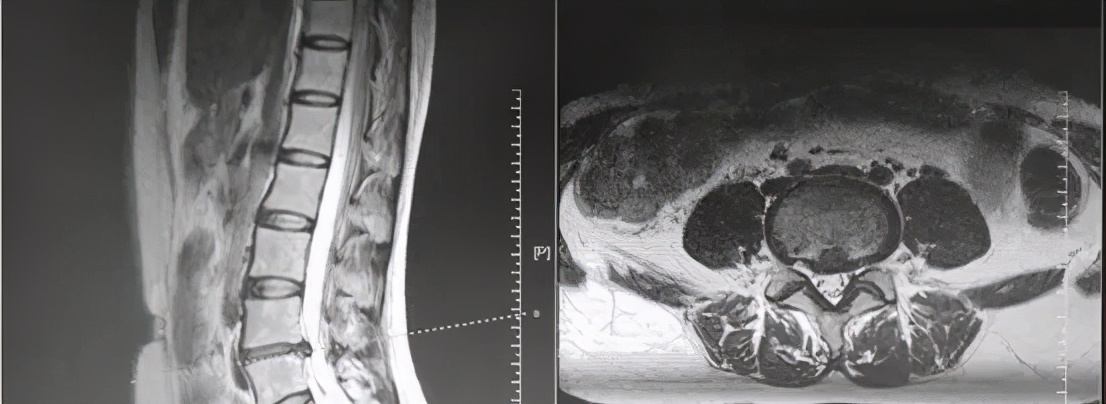

了解陈女士病史之后,林主任又详细地进行了体格检查,并仔细研究了陈女士的磁共振,通过症状、体征、影像学三方面信息的汇总,林主任判断陈女士的 腰椎间盘突出症和终板炎诊断是明确的 。

陈女士的腰椎磁共振,见轻度的腰椎间盘突出,压迫并不严重

除椎间盘突出外,尚有明显的终板炎

诊断虽然明确,但是问题也随之而来。 陈女士腰痛明显,提示终板炎亦引起了明显的症状 。